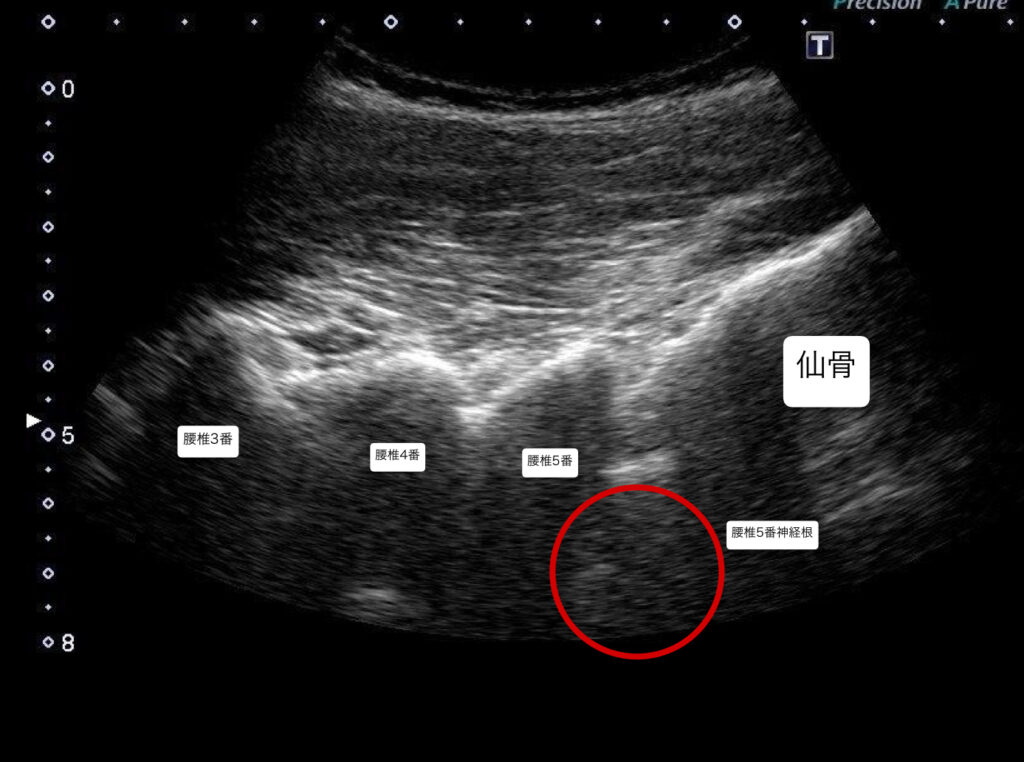

・超音波エコーで観察したところ、腰椎5番目・仙骨1番の椎間関節と仙腸関節の靭帯周囲にファシアの重責がみられた。

・坐骨神経痛の原因が腰椎5番目の神経根周囲の可能性があったため、エコーガイド下L5/S1神経根と後仙腸靭帯に対しエコー下鍼施術、鍼通電を行った。